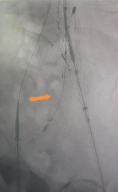

手术在全麻下进行。团队通过双侧股动脉入路,同时建立左桡动脉通路以确保精准输送。首先超选肠系膜下动脉并完成弹簧圈栓塞;随后依次释放腹主动脉主体支架、右侧髂支及IBD主体支架;最后经桡动脉路径将覆膜支架精准送入左髂内动脉并释放。术中球囊后扩张各连接处,最终造影显示:腹主动脉、双侧髂总、髂外及髂内动脉均通畅,无内漏,瘤腔完全隔绝——手术圆满成功。

之家释放后扩张

术后左髂内动脉通畅

术后第二天患者即可下床活动、正常进食;阴茎勃起功能未受影响。术后第三天顺利出院。随访至今,患者无不适,性生活恢复正常,对手术效果高度满意。